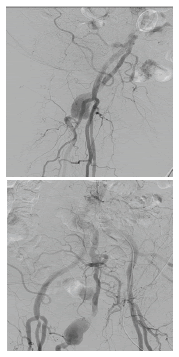

En la arteriografía (figura 1) se evidenció: una arteria ciática persistente derecha permeable, con degeneración aneurismática proximal, con recorrido por el muslo sin lesiones y unión con la arteria poplítea en su segunda porción; trombos suboclusivos en dicho aneurisma; ateromatosis de la arteria femoral superficial derecha en su tercio medio y distal, con estenosis crítica en su unión con la arteria poplítea, y llegada distal a este sitio de la arteria ciática persistente. Las arterias ilíacas y femorales izquierdas fueron normales. Se observaron trombos oclusivos en la arteria femoral superficial derecha distal, en la primera porción de la arteria poplítea, y en las arterias tibial posterior y peronea.

Se consideró que la causa de la isquemia aguda fue la embolia desde el aneurisma de la arteria ciática persistente y que la mayoría del flujo de la extremidad estaba dado por dicha arteria anómala. Con el fin de planear la corrección del aneurisma de la arteria ciática persistente, para evitar eventos isquémicos posteriores, se practicó una angiotomografía de los miembros inferiores (figura 2).